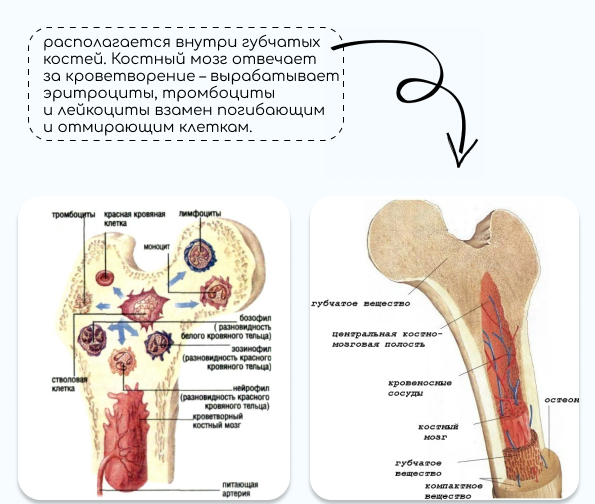

Изучение костного мозга: анатомия и функции

Раздел: Фотогалерея мыслей